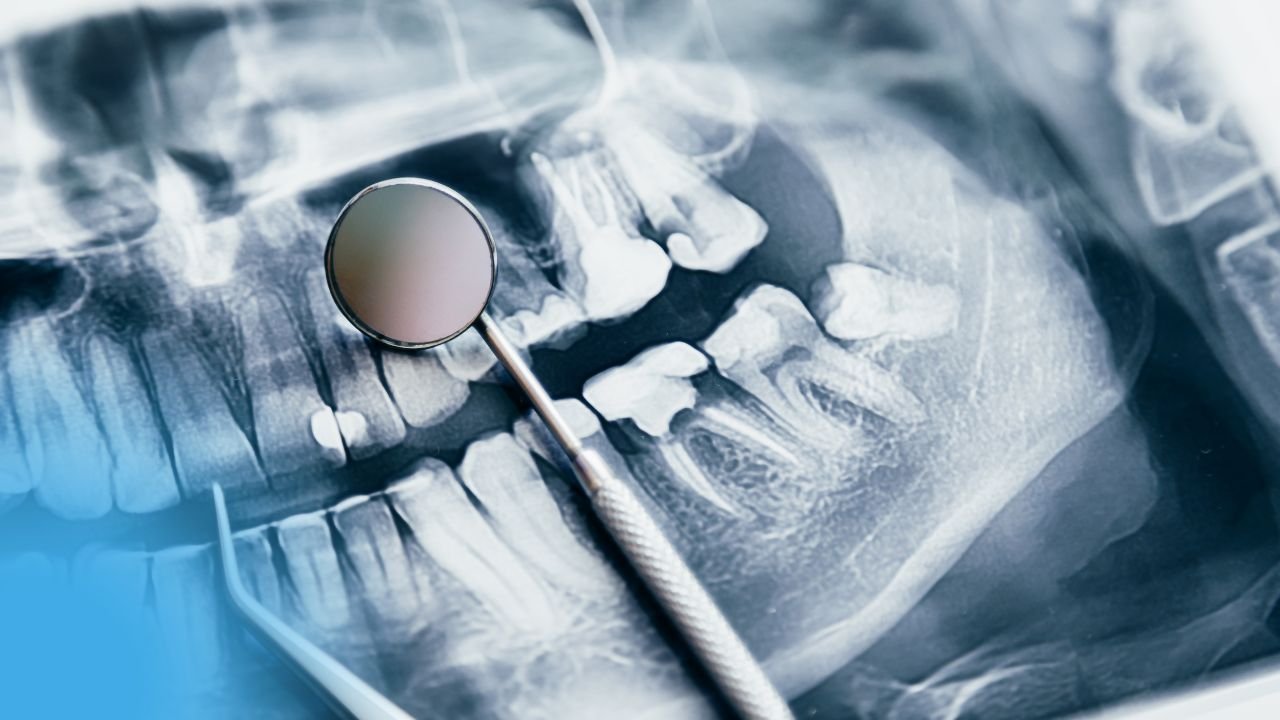

Concepts Actuels de Préparation des Cavités en Dentisterie, odontologie conservatrice et endodontie

Concepts Actuels de Préparation des Cavités en Dentisterie, odontologie conservatrice et endodontie Introduction Depuis l’apparition des systèmes adhésifs destinés aux...